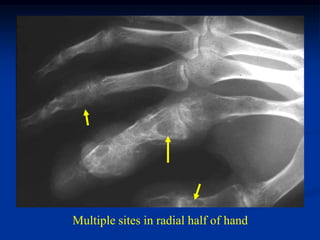

Case #575

28 year male

Ollier’s upper

extremity

Multiple sites in radial half of hand

AP x-ray